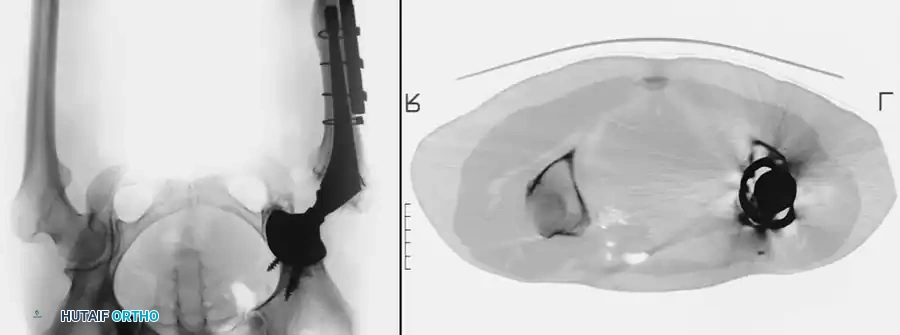

Surgical Warning: Radiation exposure must be strictly limited to the soft tissues immediately surrounding the hip joint. Potential biologic ingrowth surfaces of cementless femoral and acetabular components must be appropriately shielded to prevent catastrophic failure of osseointegration.

Hedley et al. and Kennedy et al. reported no clinical evidence of loosening, subsidence, or radiolucent lines around cementless prostheses after appropriately shielded irradiation. However, delayed union or nonunion of a trochanteric osteotomy remains a significant potential complication. Malignant transformation has not been reported with the low dosages currently recommended for prophylaxis.